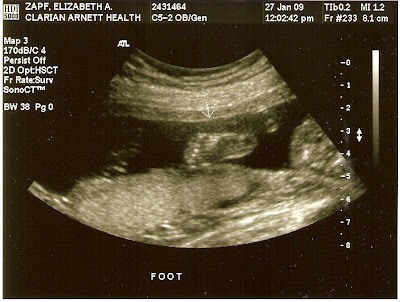

So, here is “New Baby” at 20 weeks:

I didn’t add any captions because the ultrasound tech did such a lovely job of it, I didn’t want to attempt to out-do her.